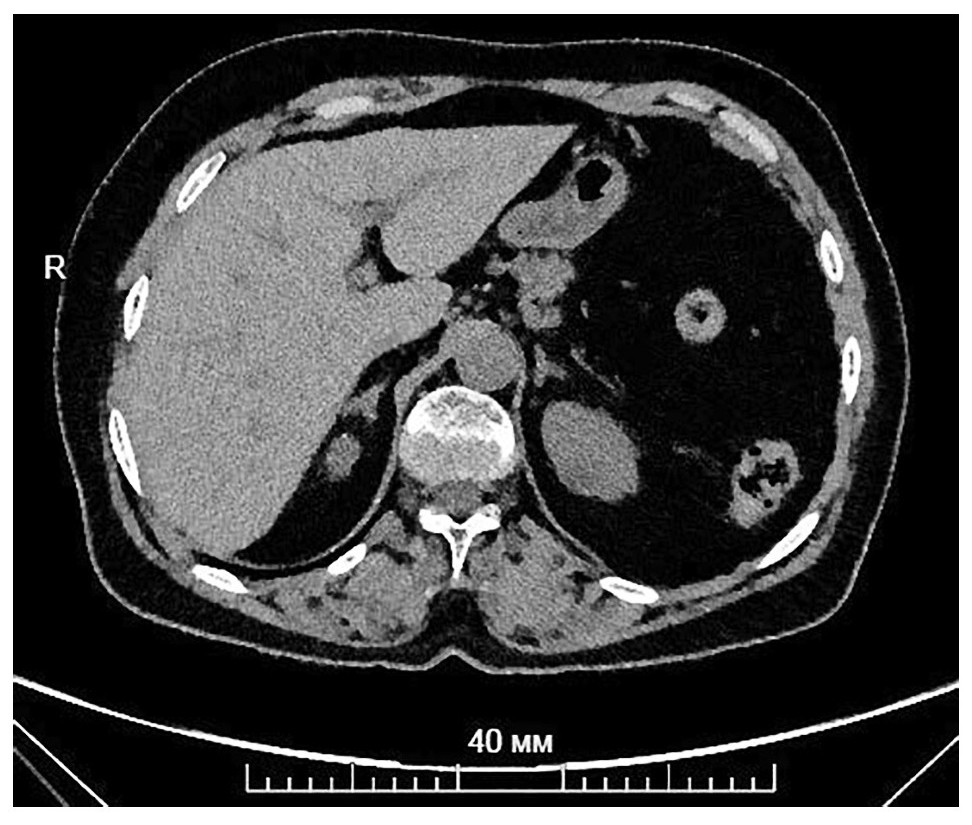

- МСКТ органов шеи, грудной клетки, брюшной полости и малого таза выявила: очаговое образование в легких – S1/2 доли слева, округлой формы, ровными контурами, размерами 9×6 мм; гиперплазия обоих надпочечников (рис. 2).

Рис. 2. МСКТ органов брюшной полости с контрастированием. Надпочечники: обычно расположены, диффузно утолщены, плотностью в нативную фазу – 28 HU, в артериальную – 97 HU, в венозную – 111 HU, в выделительную – 62 HU.

Fig. 2. Multispiral computed tomography of abdominal organs with contrast. Adrenal glands: usually located, diffusely thickened, density in the native phase – 28 HU, in the arterial phase – 97 HU, in the venous phase – 111 HU, in the excretory phase – 62 HU.